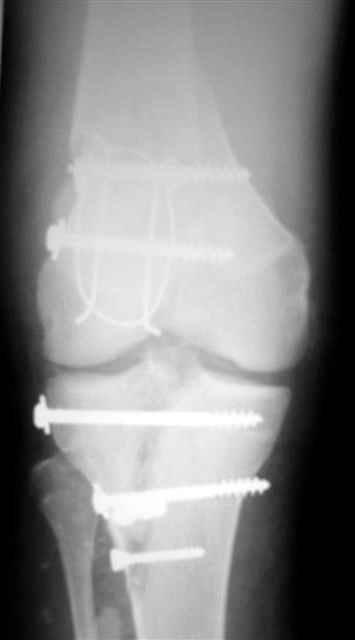

Отправитель: Evgueny Tschekashkin 14 Декабрь 2004, 18:41

Вид раны на сегодня...

4 cутки после травмы.

Спасибо за комментарии. Травма тяжелая с проблематичным прогнозом для функции коленного сустава( изначально травма разгибательного аппарата с последующим частичным некрозом собственной связки надколенника и о обнажением рефиксированного фрагмента бугристости большеберцовой кости, дефектом центрального отдела суставной поверхности большеберцовой кости и медиального отдела капсулы сустава).